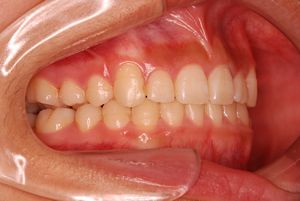

治療前 の 左 です 動く矢印治療後 の 左 です

治療前 の 右 です 動く矢印治療後 の 右 です